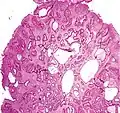

Juvenile Polyp Upper GI tract and colon Cystically dilated glands with expanded lamina propria Not inherently, may develop dysplasia